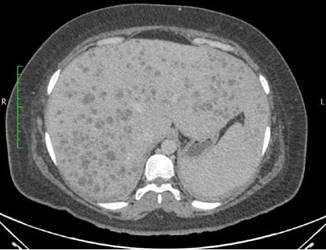

Dentro la evolución del cuadro clínico la paciente presentó una evolución estacionaria, persistiendo con taquicardia, y taquipnea, además de leucocitosis de 19 200 con neutrofolia de 95%, a pesar de haber removido la causa de la obstrucción (coledocolitiasis) y haberse administrado antibióticos (ceftriaxona 1 g EV cada 12 horas y metronidazol 500 mg EV cada 8 horas) durante 72 horas. Es así, que se realiza nueva ecografía abdominal (Figura 2) la cual reportó: “microabscesos hepaticos?, dilatación de vía biliar extrahepática hasta 18 mm y vesícula con barro biliar”, por lo que tras ser valorada por el servicio de medicina interna se decide realizar tomografía axial computarizada (TAC) de abdomen con contraste y en el contexto de una sepsis de foco abdominal por probables microabscesos hepáticos se decide rotar el esquema de tratamiento antibiótico a meropenem 1 g EV cada 8 horas, descontinuando ceftriaxona, y continuando metronidazol 500 mg EV cada 8 horas. En misma fecha se realiza TAC de abdomen con contraste (Figura 3 y 4) la cual reporta: “hepatomegalia, innumerables microabscesos hepáticos, dilatación de vía biliar intra y extrahepatica, a descartar engrosamiento de la pared lateral izquierda de la vesícula biliar, ganglios periportales de etiología por determinar (origen inflamatorio vs metastásico) y mínimo derrame pleural bilateral”. Posteriormente, se solicitan marcadores tumorales de CA 19.9, CA 125, AFP y CEA, todos ellos con resultados dentro de parámetros normales.

Fuente: examen de la paciente realizado en centro de imagen extrainstitucional.

Figura 3. Tomografía axial computarizada de abdomen con contraste (corte axial) que evidencia la presencia de múltiples microabscesos distribuidos en ambos lóbulos hepáticos.